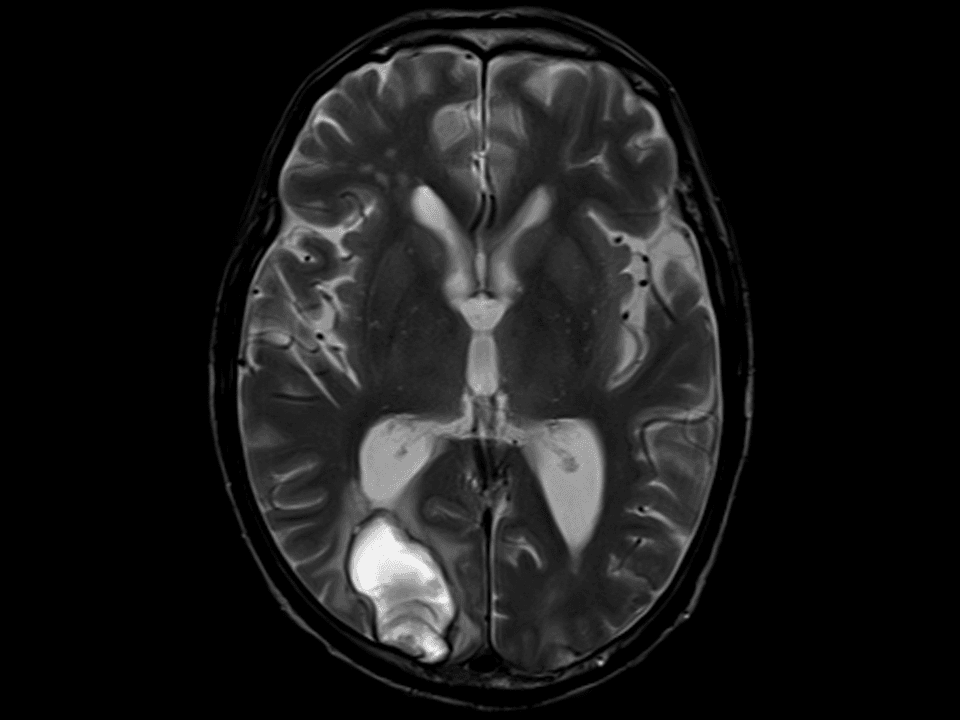

Excellent performance and pristine image quality for standard and adv. applications like functional imaging(BOLD),prefusion or diffusion tensor imaging and tractography.